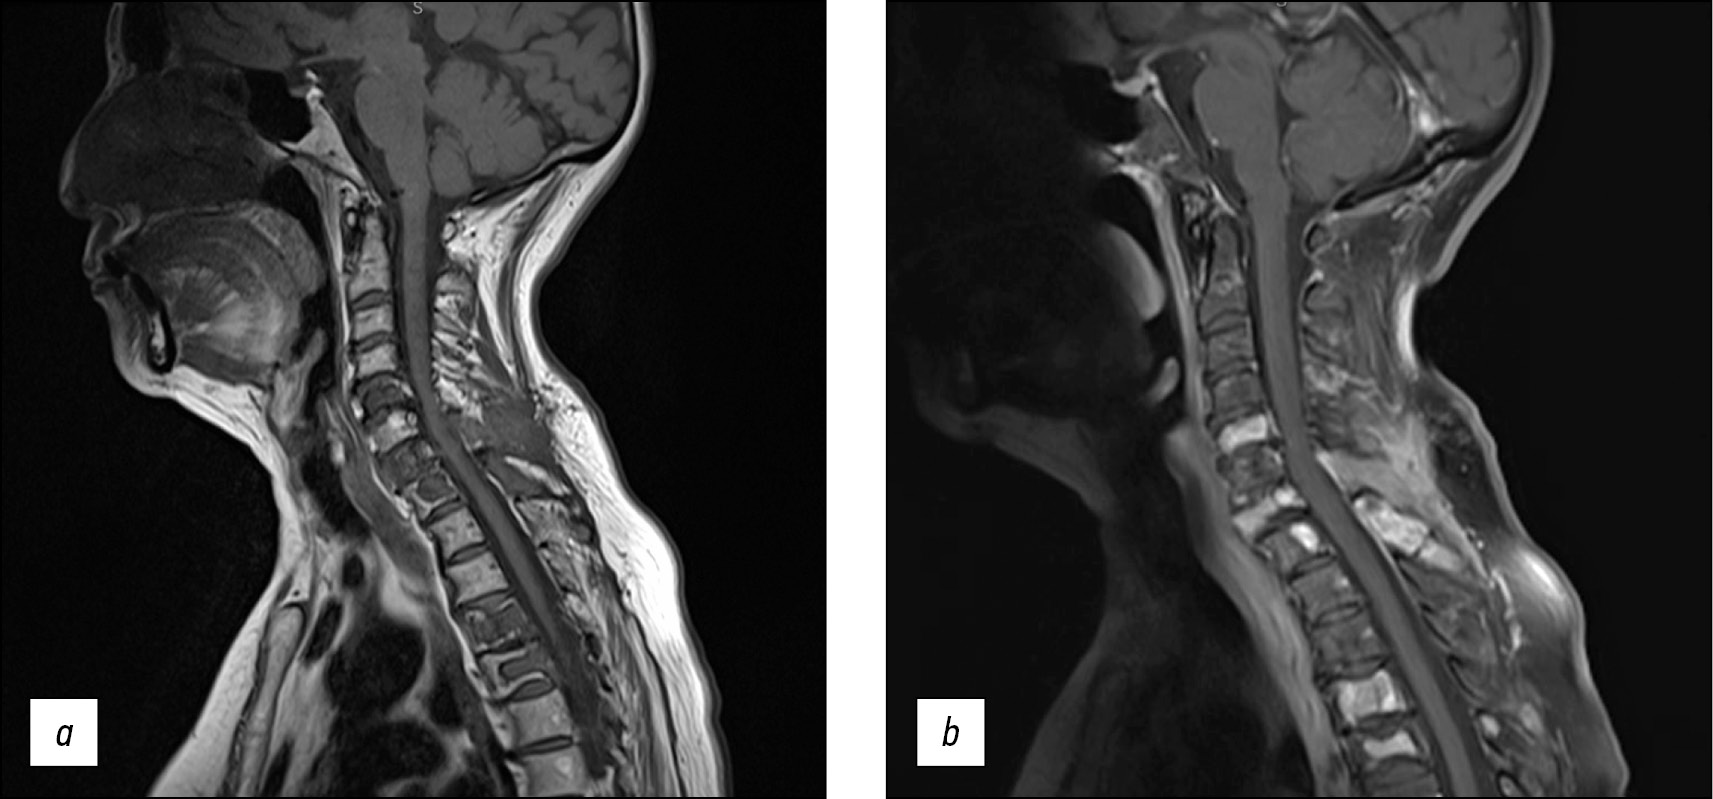

The MRI, even if not straight and not particularly useful for the differential diagnosis, was performed, thus confirming the polyostotic skeletal involvement.

It showed T1 hypointense lytic lesions at the level of C5, C7, D1, D4, and D5 vertebrae, with involvement of posterior elements of C5–C6 (Fig. 3a) and a corresponding heterogeneous contrast enhancement in T1w sequences after Gadolinium administration (Fig. 3b). The bone tissue showed extensive remodeled areas, without confirmed periosteal reaction.

Fig. 3. Sagittal T1w sequence of the cervical tract shows heterogeneously low-signal bone lytic lesions involving C5, C7, D1, D4, and D5 vertebrae and the spinous processes of C5 and C6 metamers (3a); all these findings were also confirmed by the administration of Gadolinium contrast enhancement (3b).